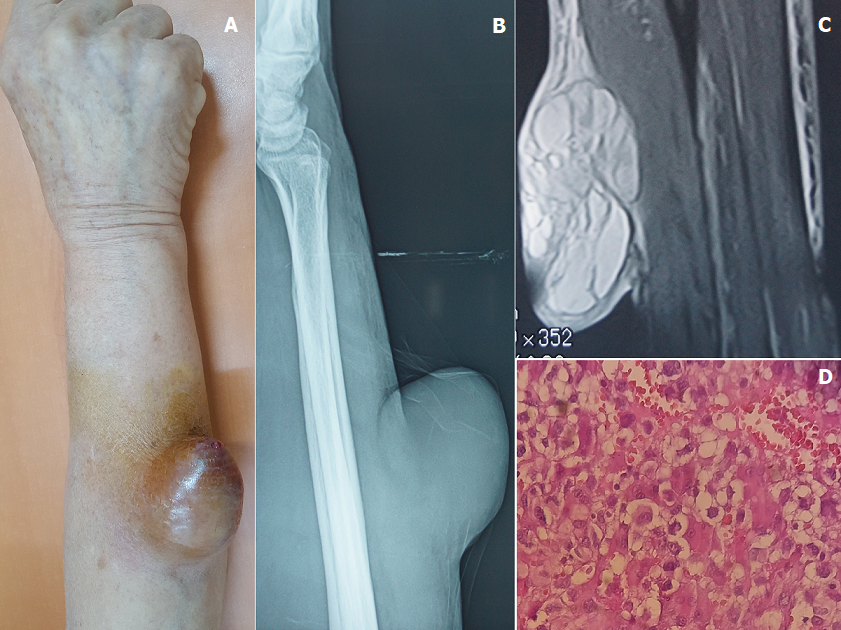

Synovialosarcome de l’avant-bras droit

Patiente âgée de 60 ans, suivis pour cardiomyopathie hypertensive depuis 04 ans, qui a consulté en dermatologie pour une masse de l’avant-bras droit évoluant depuis un an et augmentant progressivement de taille. L’examen clinique a objectivé une lésion tumorale molle, arrondie, volumineuse mesurant 8 centimètres au grand diamètre, indolore, fixe par rapport aux deux plans, à surface ulcéro-crouteuse et siégeant au niveau du tiers moyens de la face postéro-latérale de l’avant-bras droit (A). La radiographie standard a objectivé une masse opaque homogène respectant la corticale en regard (B). L’Imagerie par résonnance magnétique était en faveur d’un volumineux processus cutanéo-sous cutané à double composante tissulaire et kystique multi-cloisonnée infiltrant la graisse sous cutanée et arrivant en contact intime avec les muscles extenseurs (C). L’histologie a objectivé une prolifération sarcomateuse peu différenciée à cellules pléomorphes (D) complétée par une étude Immuno-histochimique qui a confirmé le diagnostic d’un Synovialo-sarcome. La patiente a été adressée en chirurgie plastique pour bénéficier d’un traitement chirurgical.